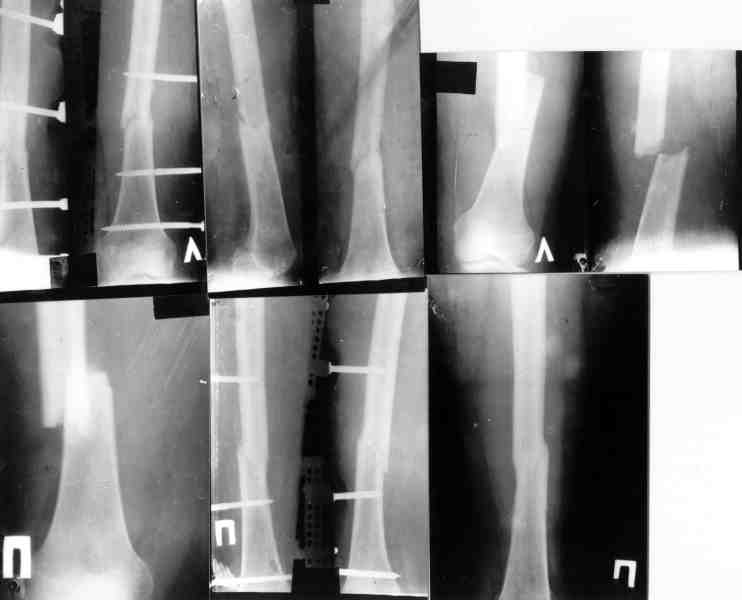

Re: Огнестрельный перелом плеча ( продолжение)

Вот еще информация, ознакамливайтесь pls/